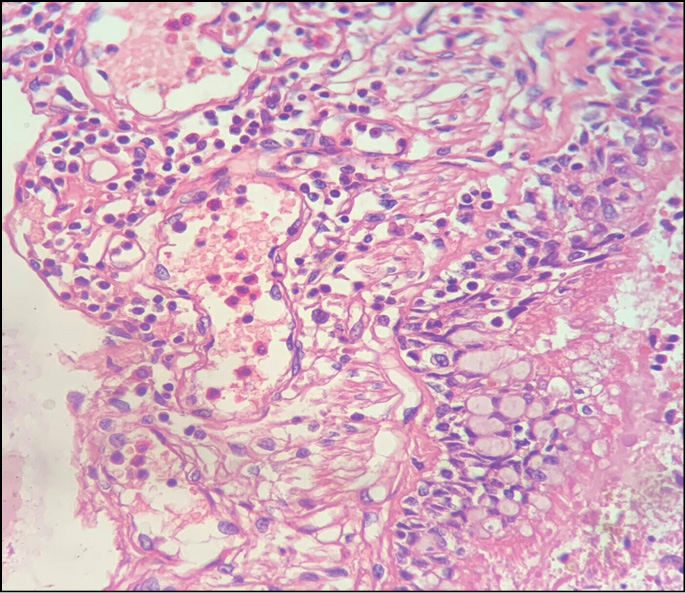

- очаги острой альвеолярной эмфиземы, дистелек-тазов, серозного отёка, интерстициального воспаления; мелкоочаговый альвеолит; нарушение гемодинамики в системе микроциркуляторного русла; в просветах сосудов эозинофилия разной степени выраженности (рис. 2); стенки бронхов с небольшой полиморфноклеточной инфильтрацией, наличием эозинофильных лейкоцитов (рис. 3); спазм бронхов и бронхиол (рис. 4), в просветах части бронхиол ― гомогенные бурые массы, клетки десквамированного эпителия (рис. 5); отёк висцеральной плевры;

Рис. 2. Скопление эозинофильных лейкоцитов в просветах сосудов лёгких. Окраска гематоксилином и эозином, ×100.